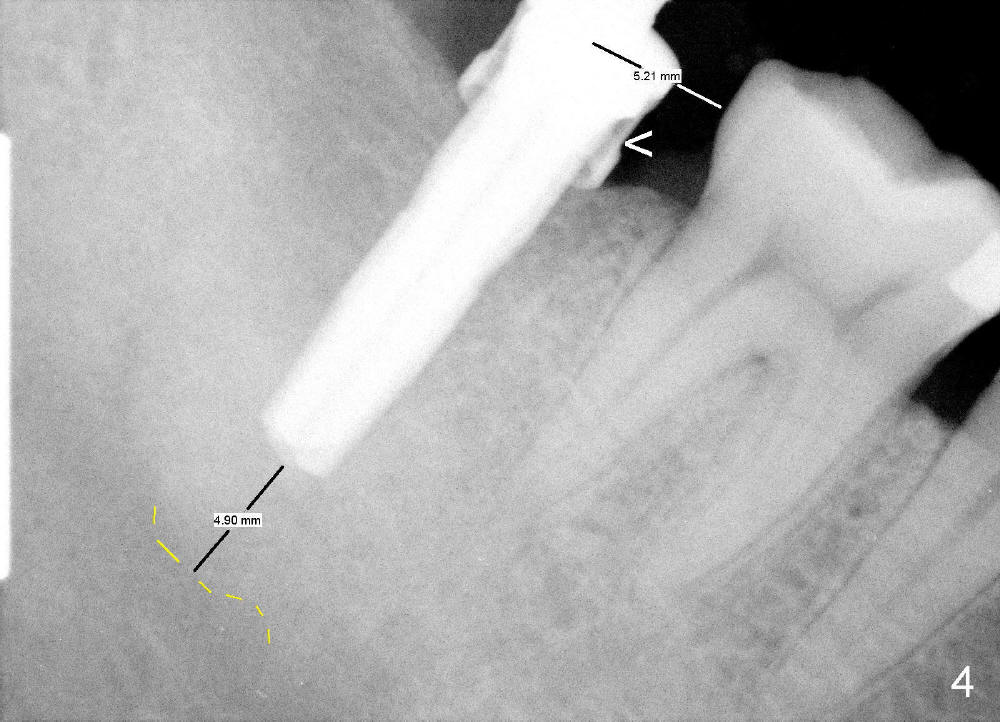

A 53-year-old man requests implant restoration for the lower right 2nd molar (Fig.1: LR2). A 5.3x14 mm submerged tapered implant is planned (Fig.2). PA is taken with a parallel pin after use of a 2 mm drill at the depth of 12 mm (Fig.3). It appears that the length of 14 mm has a safe margin (2-3 mm from the inferior alveolar nerve, yellow dashed line). In addition, the distance from the distal surface of the 1st molar is within normal limit (~5 mm).

With these two parameters under control, it is quick and safe to finish osteotomy with tapered drills with stoppers (Fig.4 <). Stoppers are particularly useful in the posterior region where visibility is limited. The implant is placed as planned (Fig.5, as compared to Fig.2).